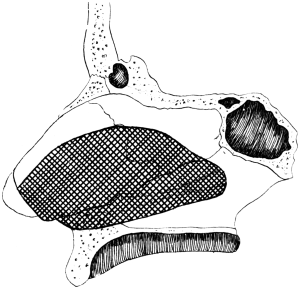

| 110. | The Normal Angle of the Anterior Chamber | 217 |

| 111. | The Angle of the Anterior Chamber from a Case of Recent Glaucoma | 218 |

| 112. | The Angle of the Chamber in a Case of Chronic Glaucoma | 219 |